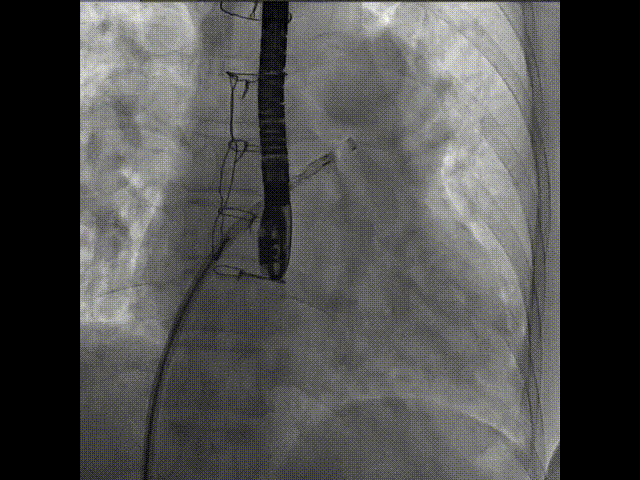

術(shù)中首先在局麻下穿刺股動脈、股靜脈,完成心導(dǎo)管檢查評估后轉(zhuǎn)為全麻,在食道超聲引導(dǎo)下穿刺房間隔,穿刺成功后將加硬導(dǎo)絲送入左上肺靜脈建立軌道,根據(jù)患者病情行球囊預(yù)擴(kuò)張后植入6mm孔徑房間隔造孔支架,經(jīng)透視及食道超聲評估支架左右盤展開良好,夾持于房間隔兩側(cè),固定穩(wěn)定、位置良好,食道彩超顯示房水平右向左為主分流,分流孔直徑符合預(yù)期大小,心導(dǎo)管檢查評估達(dá)到預(yù)期效果,釋放造孔支架。術(shù)后12h患者下床活動,恢復(fù)順利,擬于近日完善術(shù)后評估后出院。